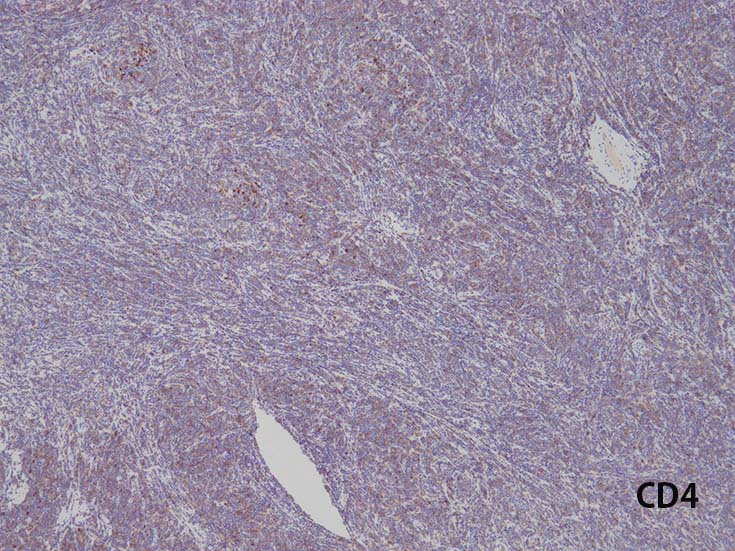

- CD1a, CD2, surface CD3 (dim), CD4, CD5, CD8は種々の程度に発現する.

- T-ALL はしばしば, CD4とCD8の double positive となる. またCD10が陽性になる

- CD4,CD8 double positiveはT-prolymphocytic leukaemiaでも認められる. CD10もPTCL(第一にはAITL)に陽性となることに注意.